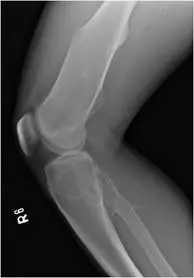

20 歲男性,因右膝受傷接受 X光攝影。附圖為 X光攝影影像,最可能的診斷為何?

遺傳性多發性外生骨疣(hereditary multiple exostoses, HME),又稱遺傳性多發性骨軟骨瘤(hereditary multiple osteochondromas, HMO),是一種體染色體顯性遺傳疾病,特徵為多個骨軟骨瘤在全身長骨的骨骺端(metaphysis)對稱性或不對稱性形成。本題考核膝關節 X 光上多發性骨突病灶的診斷辨識。

膝關節正位及側位 X 光顯示以下特徵:

側位(Lateral view):

- 確認骨突突起的立體位置及範圍

- 骨突朝遠離關節方向生長(away from joint),此為骨軟骨瘤的特徵性生長方向

- 骨性突起邊界清楚,骨皮質連續

多發性、對稱性分佈、骨骺端發生、骨皮質連續延伸的骨性突起,高度